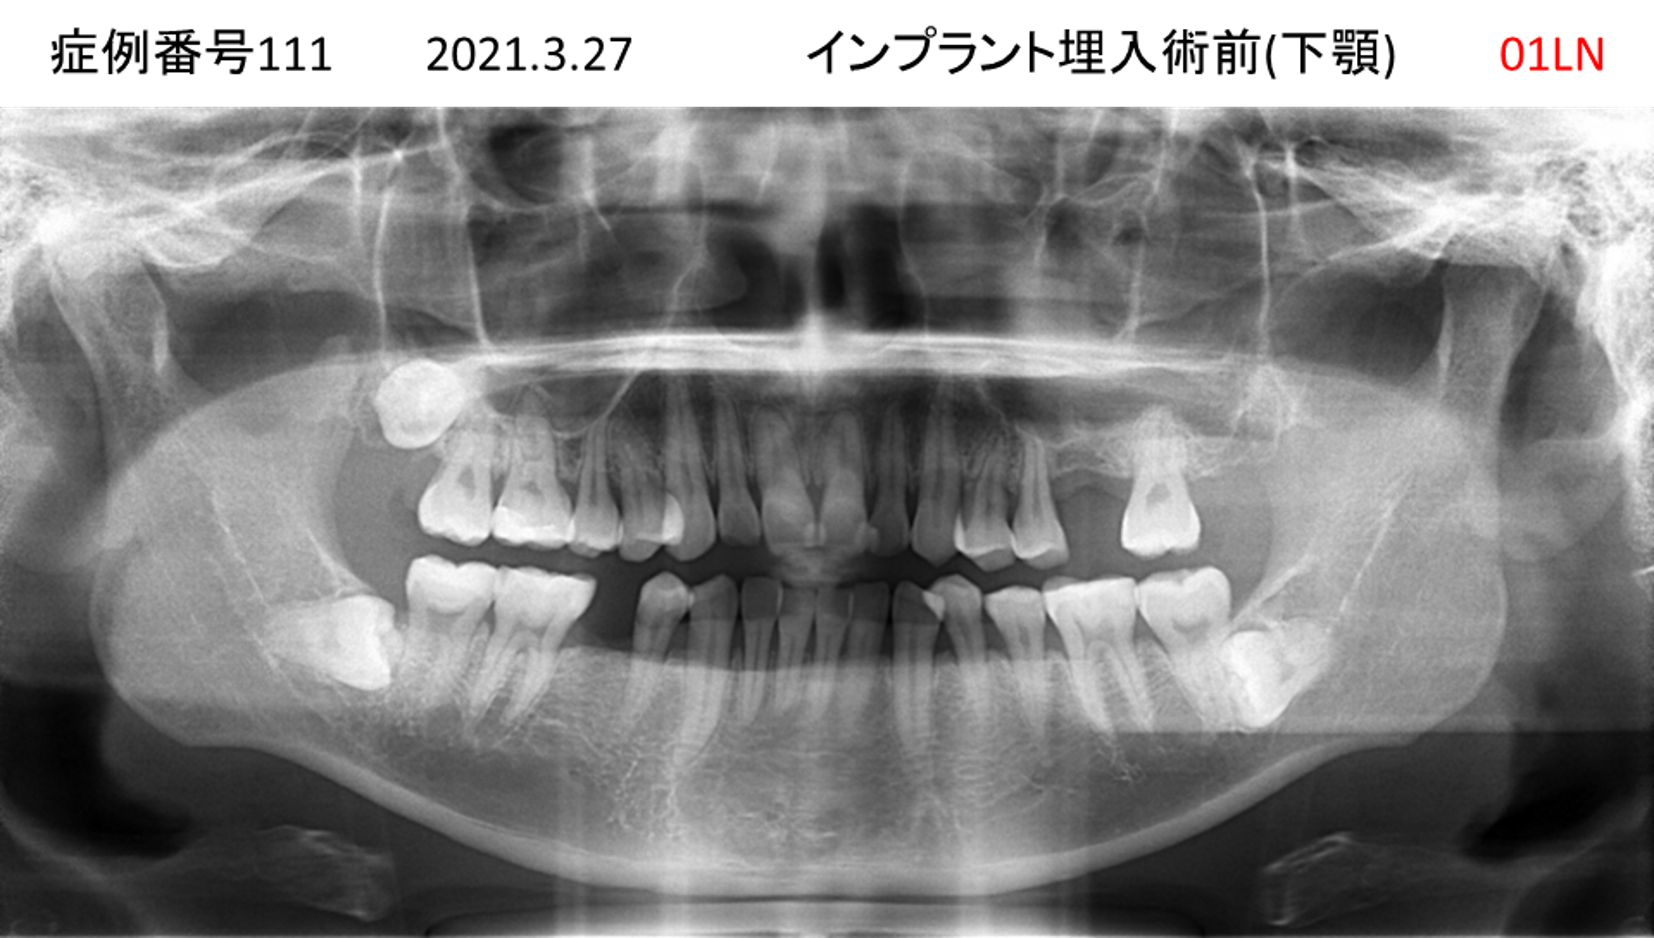

奥歯で噛めない患者様のインプラント症例

| 治療名称 |

インプラント |

| 治療費用 |

365万円+税 |

| 治療期間 |

5か月 |

| 患者さんの症状(主訴) |

奥歯で噛めない。上の前歯が揺れてきた。 |

| 治療内容 |

抜歯即時インプラント |

| 治療結果 |

食事に困らない。見た目がとても良くなった。 |

| 治療の注意点(リスク/副作用) |

インプラントが壊れたら再治療が必要 |